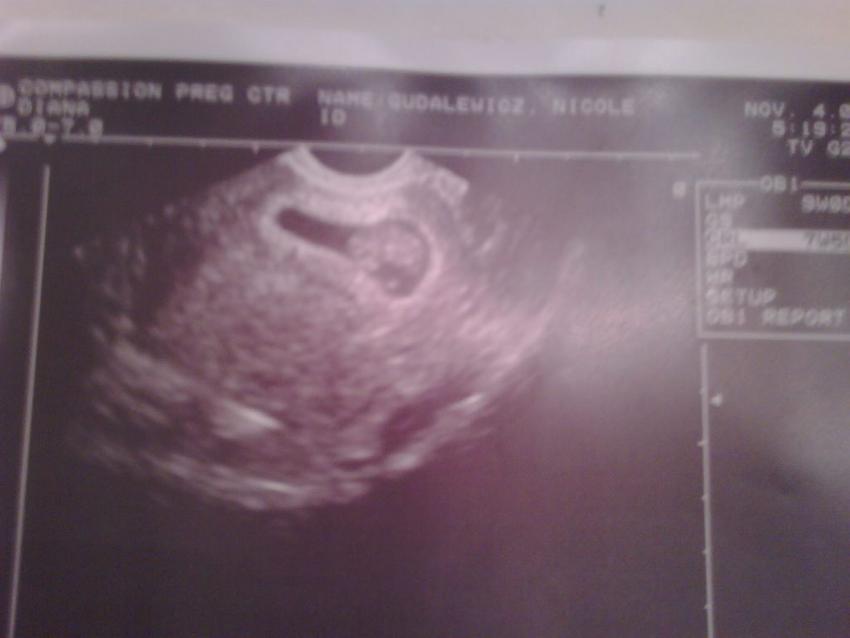

ok well maybe not....but exciting for me!!!! first images of the new kiddo!!!!